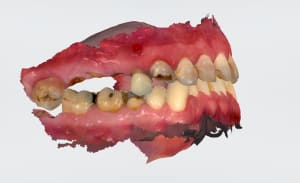

Chirurgie guidée mise en charge immédiate 005.jpg

Chirurgie guidée mise en charge immédiate 004.jpg

Chirurgie guidée mise en charge immédiate 003.jpg